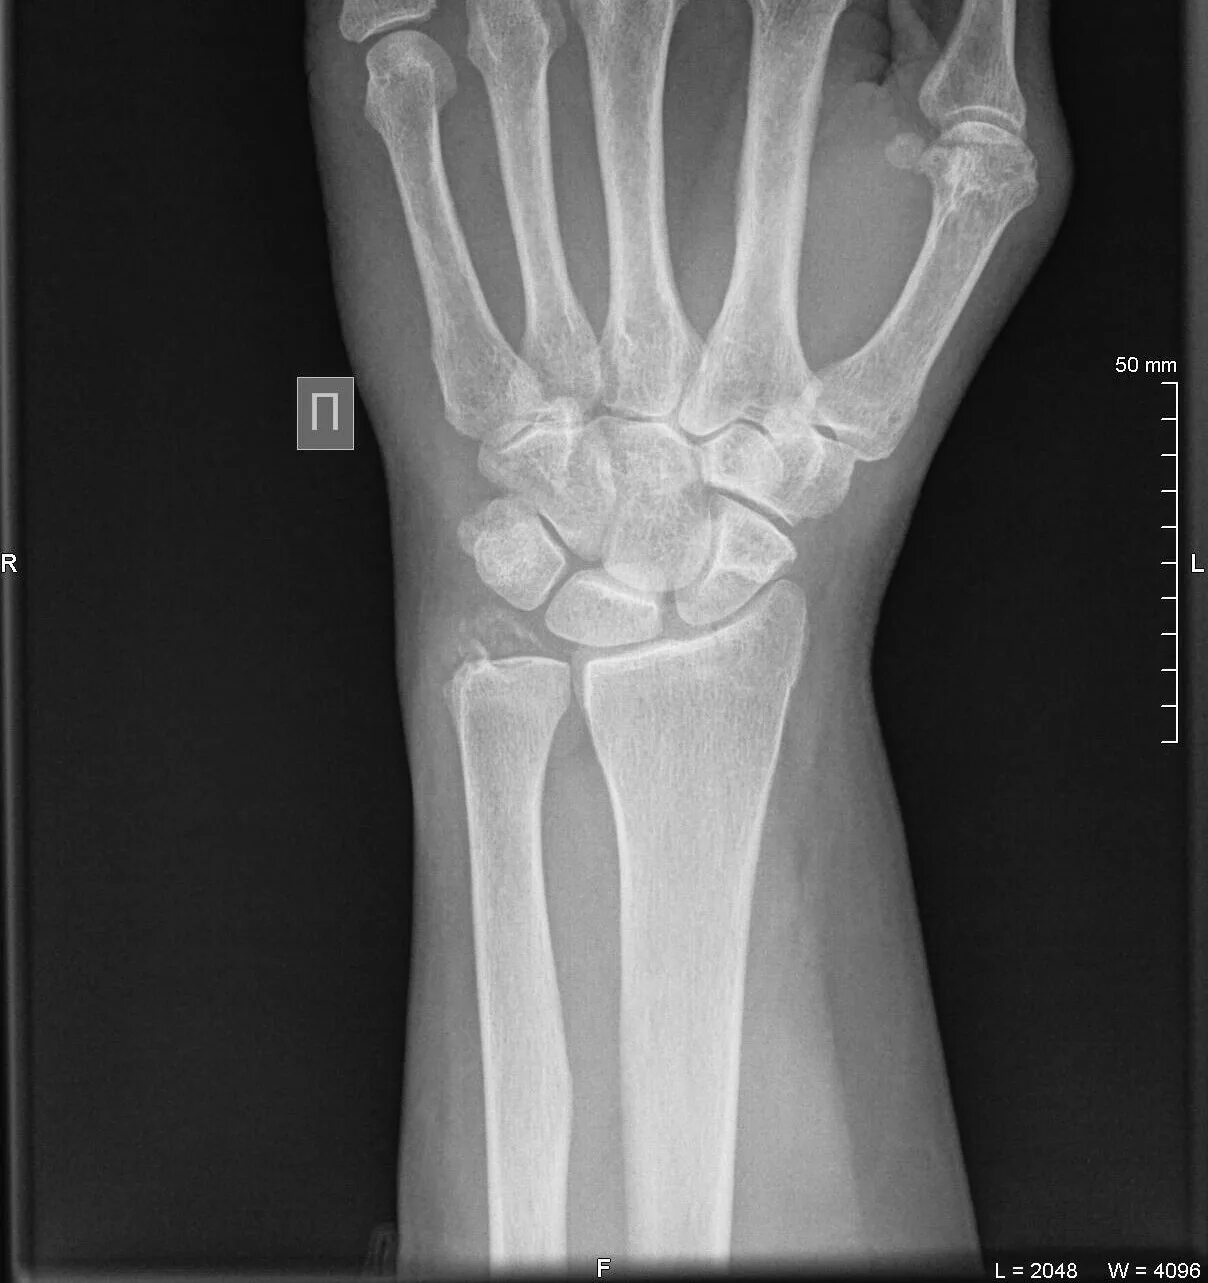

Артроз лучезапястного сустава 2 степени